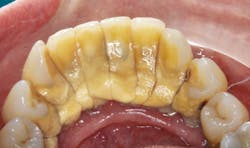

I have this plaque (no pun intended) hanging in my office: “If you ignore them, they will go away.” So, when this 57-year-old woman told me that it had been 40 years since she’d seen a dentist, I absolutely believed her. Her chief complaint: My teeth are moving. She has 70% to 90% generalized bone loss with severe mobility, and she wants a miracle. The catch? Her finances are limited.